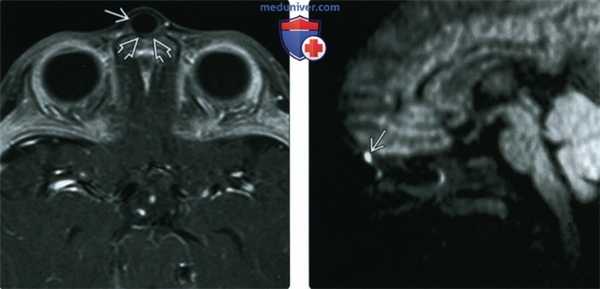

(Слева) При аксиальной МРТ Т1 С+ FS у четырехмесячного младенца с объемным образованием переносицы визуализируется дермоидная киста с «жидкостной» интенсивностью сигнала, не накапливающая контраст, приводящая к легкому ремоделированию нижележащих костей носа.

(Справа) При сагиттальной МРТ DWI визуализируется эпидермоидная киста в области слепого отверстия в виде гиперинтенсивного фокуса ограничения диффузии. Второе (экстраназальное) образование не визуализируется из-за артефактов восприимчивости на границе газа и кости.